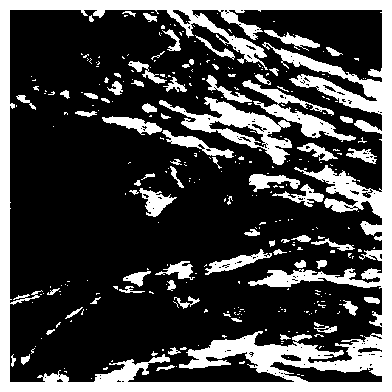

2.3 Image Annotations are an Effective Source of Privileged Information

We find that TriDeNT ♆ is effective not only for integrating additional sources of data, but also for manually determining the most useful aspects of the data which should be learned, where the user has some prior knowledge to incorporate into the dataset. This is intuitively the opposite of traditional machine learning approaches, where the user has to handcraft inputs to be passed to the model, and the model only learns from those features. With our approach, the user can manually handcraft inputs, such as the segmentation masks in this example, while still giving the model the flexibility to learn other features not known a priori to the user. The results in Table 2 demonstrate that TriDeNT ♆ is able to train encoders which retain the features of both the nuclei and the background/connective tissue. We see performance improvements of up to 42.4% compared to the privileged baseline, and up to 5.2% compared to the unprivileged baseline.

These results also suggest that, in the privileged Siamese case, the features that are learned are those relating to the shape of the nuclei, rather than any sub-nuclear features or features relating to the connective tissue which would enable better identification of tissue and cell types.

We also analyse the activation maps for each model using GradCAM as described in section S3. This offers more insight into the areas of the image which are contributing most heavily to the models’ representations. In Figure 4(b) we present some representative examples, however, a larger selection which was chosen at random is presented in Figures S10 to S25. The larger selection makes it easier to see the emergent patterns, including that privileged Siamese models tend to mainly identify features which are strongly present in both inputs, while unprivileged Siamese models tend to learn more diffuse features that are not specific to one cell phenotype or image region. TriDeNT ♆ incorporates both sets of features, learning both features specific to the privileged data and more the general features associated with unprivileged Siamese networks.

We can see in Figure 4(b) panel A that for ERG, the privileged Siamese model focuses almost exclusively on any nuclei which could be endothelial cells. As there are very few endothelial cells in the dataset, it could be an effective strategy to identify anything that could potentially be an endothelial cell to minimise the difference between the representations of the H&E model and the IF mask model. In the corresponding unprivileged Siamese image, we see that the model identifies some of these nuclei, albeit less strongly, but also focuses heavily on the other tissue and even the background, while strongly fixating on two spots of debris in the center of the image. This model has less ‘incentive’ to learn the weak features related to endothelial cells as these occur rarely and are not easy to detect, while more generic strong features such as the presence of connective tissue and the prevalence of background are more common and predictable from augmented images. We see that TriDeNT ♆ combines these two feature sets, strongly identifying nuclei while also identifying the connective tissue.

In panel C we see a similar pattern, with the privileged Siamese model fixating solely on the nuclei, while the TriDeNT ♆ model takes a more balanced approach. The unprivileged Siamese model appears to focus on a single cluster of nuclei while neglecting others, and similarly identifies an area of fibroblasts with its distinctive pattern but does not others.

In contrast to panels A and C which represent models with poor privileged Siamese results, panels B and D represent models whose privileged Siamese results were comparable to both TriDeNT ♆ and even the supervised baseline. It is therefore interesting to note that there are far more similarities between the privileged Siamese and TriDeNT ♆ models in both cases. Particularly in panel B, TriDeNT ♆ and the privileged Siamese model return virtually identical heatmaps, with both strongly identifying epithelial nuclei and neglecting the same areas of connective tissue. The unprivileged model in this case appears to focus solely on the centre of the image, giving a significantly different heatmap to the other panels.

Panel D again shows the previous pattern, with the privileged Siamese model identifying the features strongly present in the privileged data – fibroblasts – while neglecting the nuclei present. TriDeNT ♆ also strongly identifies the connective tissue, but, unlike the privileged Siamese model, does not completely neglect the nuclei. The unprivileged Siamese model primarily identifies background, and does not appear to identify the nuclei in this example.

We paired H&E images with corresponding thresholded IF images of the same (restained) patch from the SegPath dataset [22]. IF images were obtained by thresholding IF intensity, such that pixels with lower intensity than the cutoff were labelled 0 and those higher than the cutoff were labelled 1. For ease of computing and consistency of size with evaluation datasets, we resized each px image to px with linear interpolation, and split these into 16 px patches, and did the same for each corresponding mask. Each input was a tuple , with both and being px (pixel) patches from the same location on both the H&E and restained slides. Given that no evaluation was to be performed directly on the SegPath dataset, the train, validation and test sets were combined to increase the dataset size, with the number of patches for each stain after preprocessing detailed in Table S1.